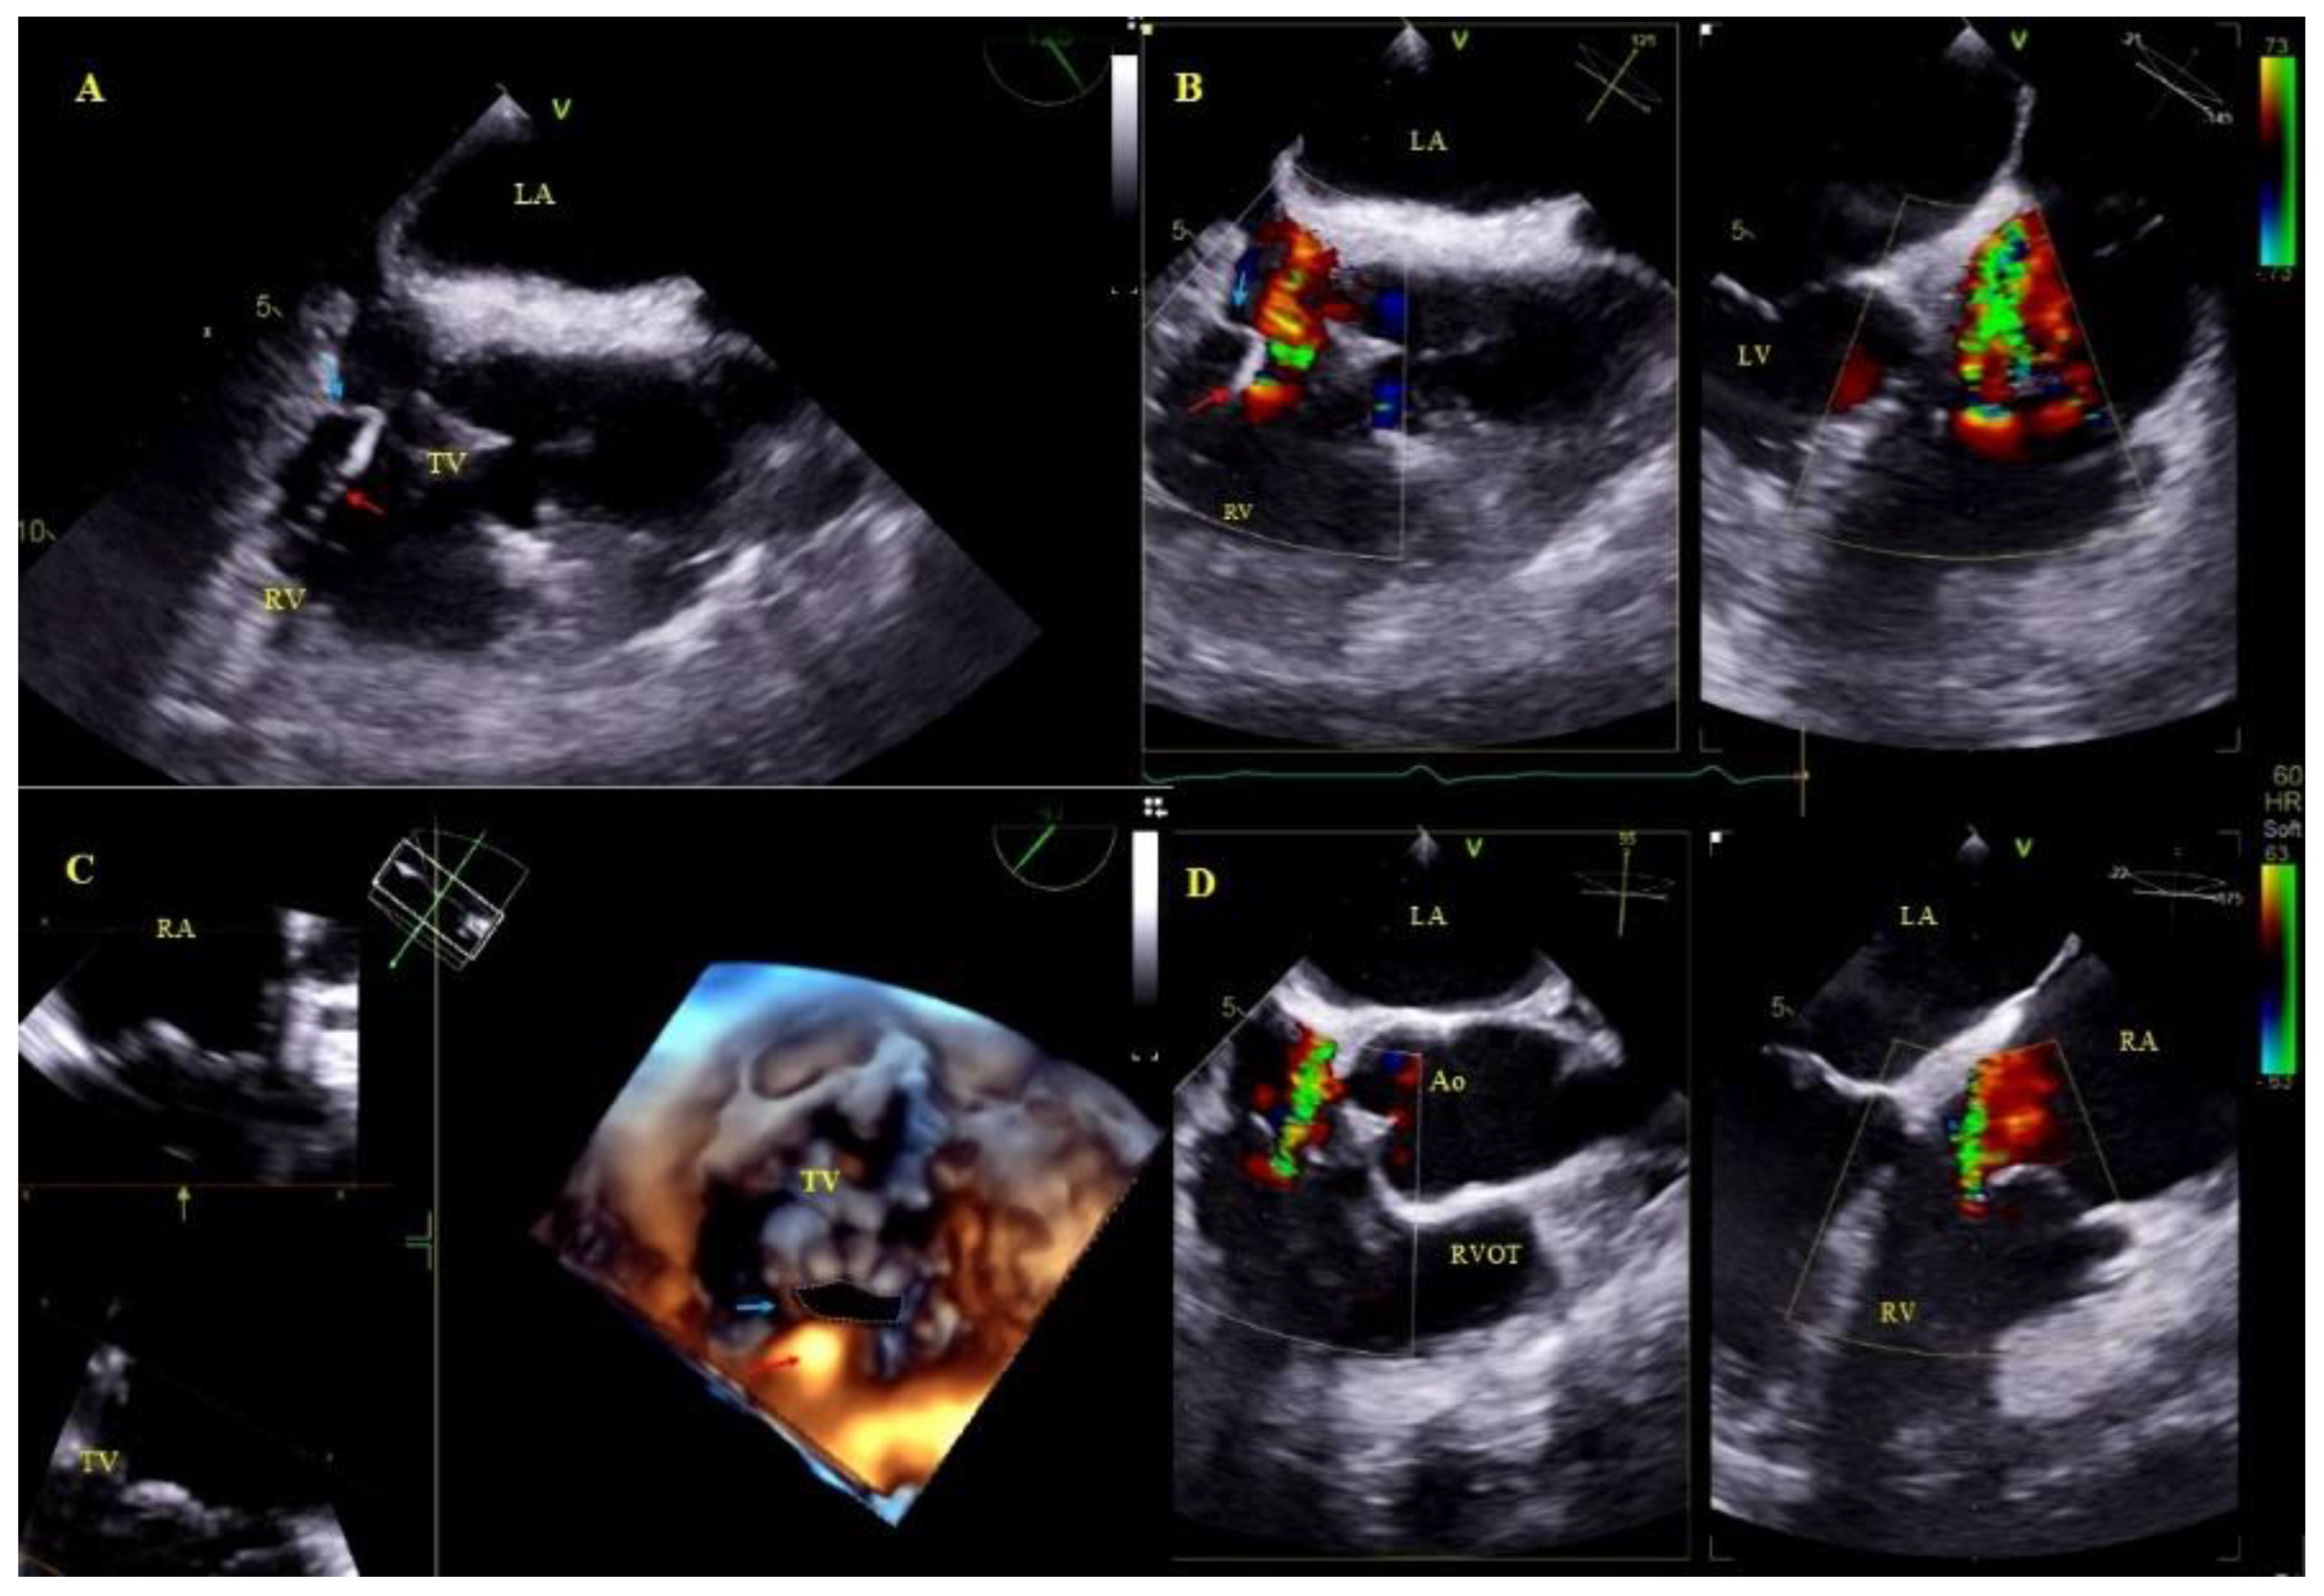

2.5. Echocardiographic Findings Associated with Endocardial Leads: Definition and Classification According to the Anatomy and Characteristic Features